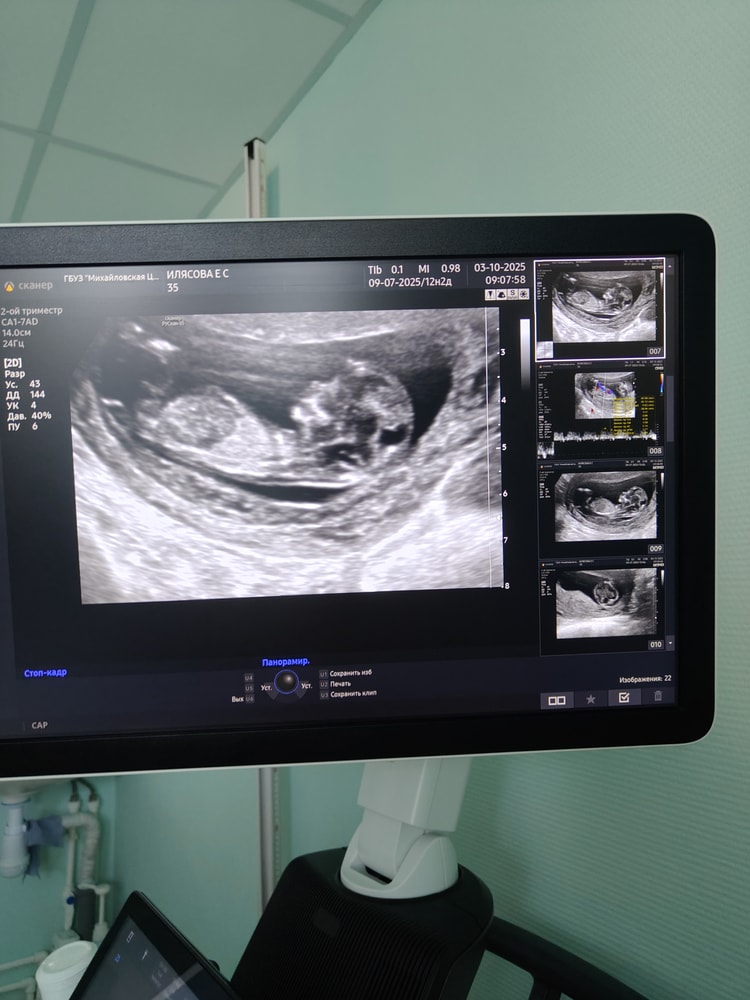

Беременность вторая, первая была анэмбриония. Долгожданная и желанная. Сегодня прошел первый скрининг, развитие малыша по сроку, всё хорошо, кроме гипертонуса (думаю что ответ на узи датчик, и плюс поездка, скрининг был в другом городе) и предлежание плаценты, будем ждать второго скрининга в покое теперь. Скрининг прошел молча, лишь было сказано, что всё хорошо.

Хотела бы погадать кто будет, мальчик или девочка)